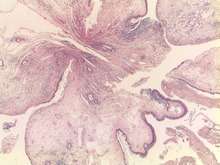

Nasal polyps consist of hyperplastic oedematous connective tissue with some seromucous glands and inflammatory cells (mostly neutrophils and eosinophils) with respiratory epithelium, sometimes with metaplastic squamous epithelium on the surface.Nasal polyps should be distinguished from nasal papillomas, which are benign epithelial tumors and have more serious consequences.